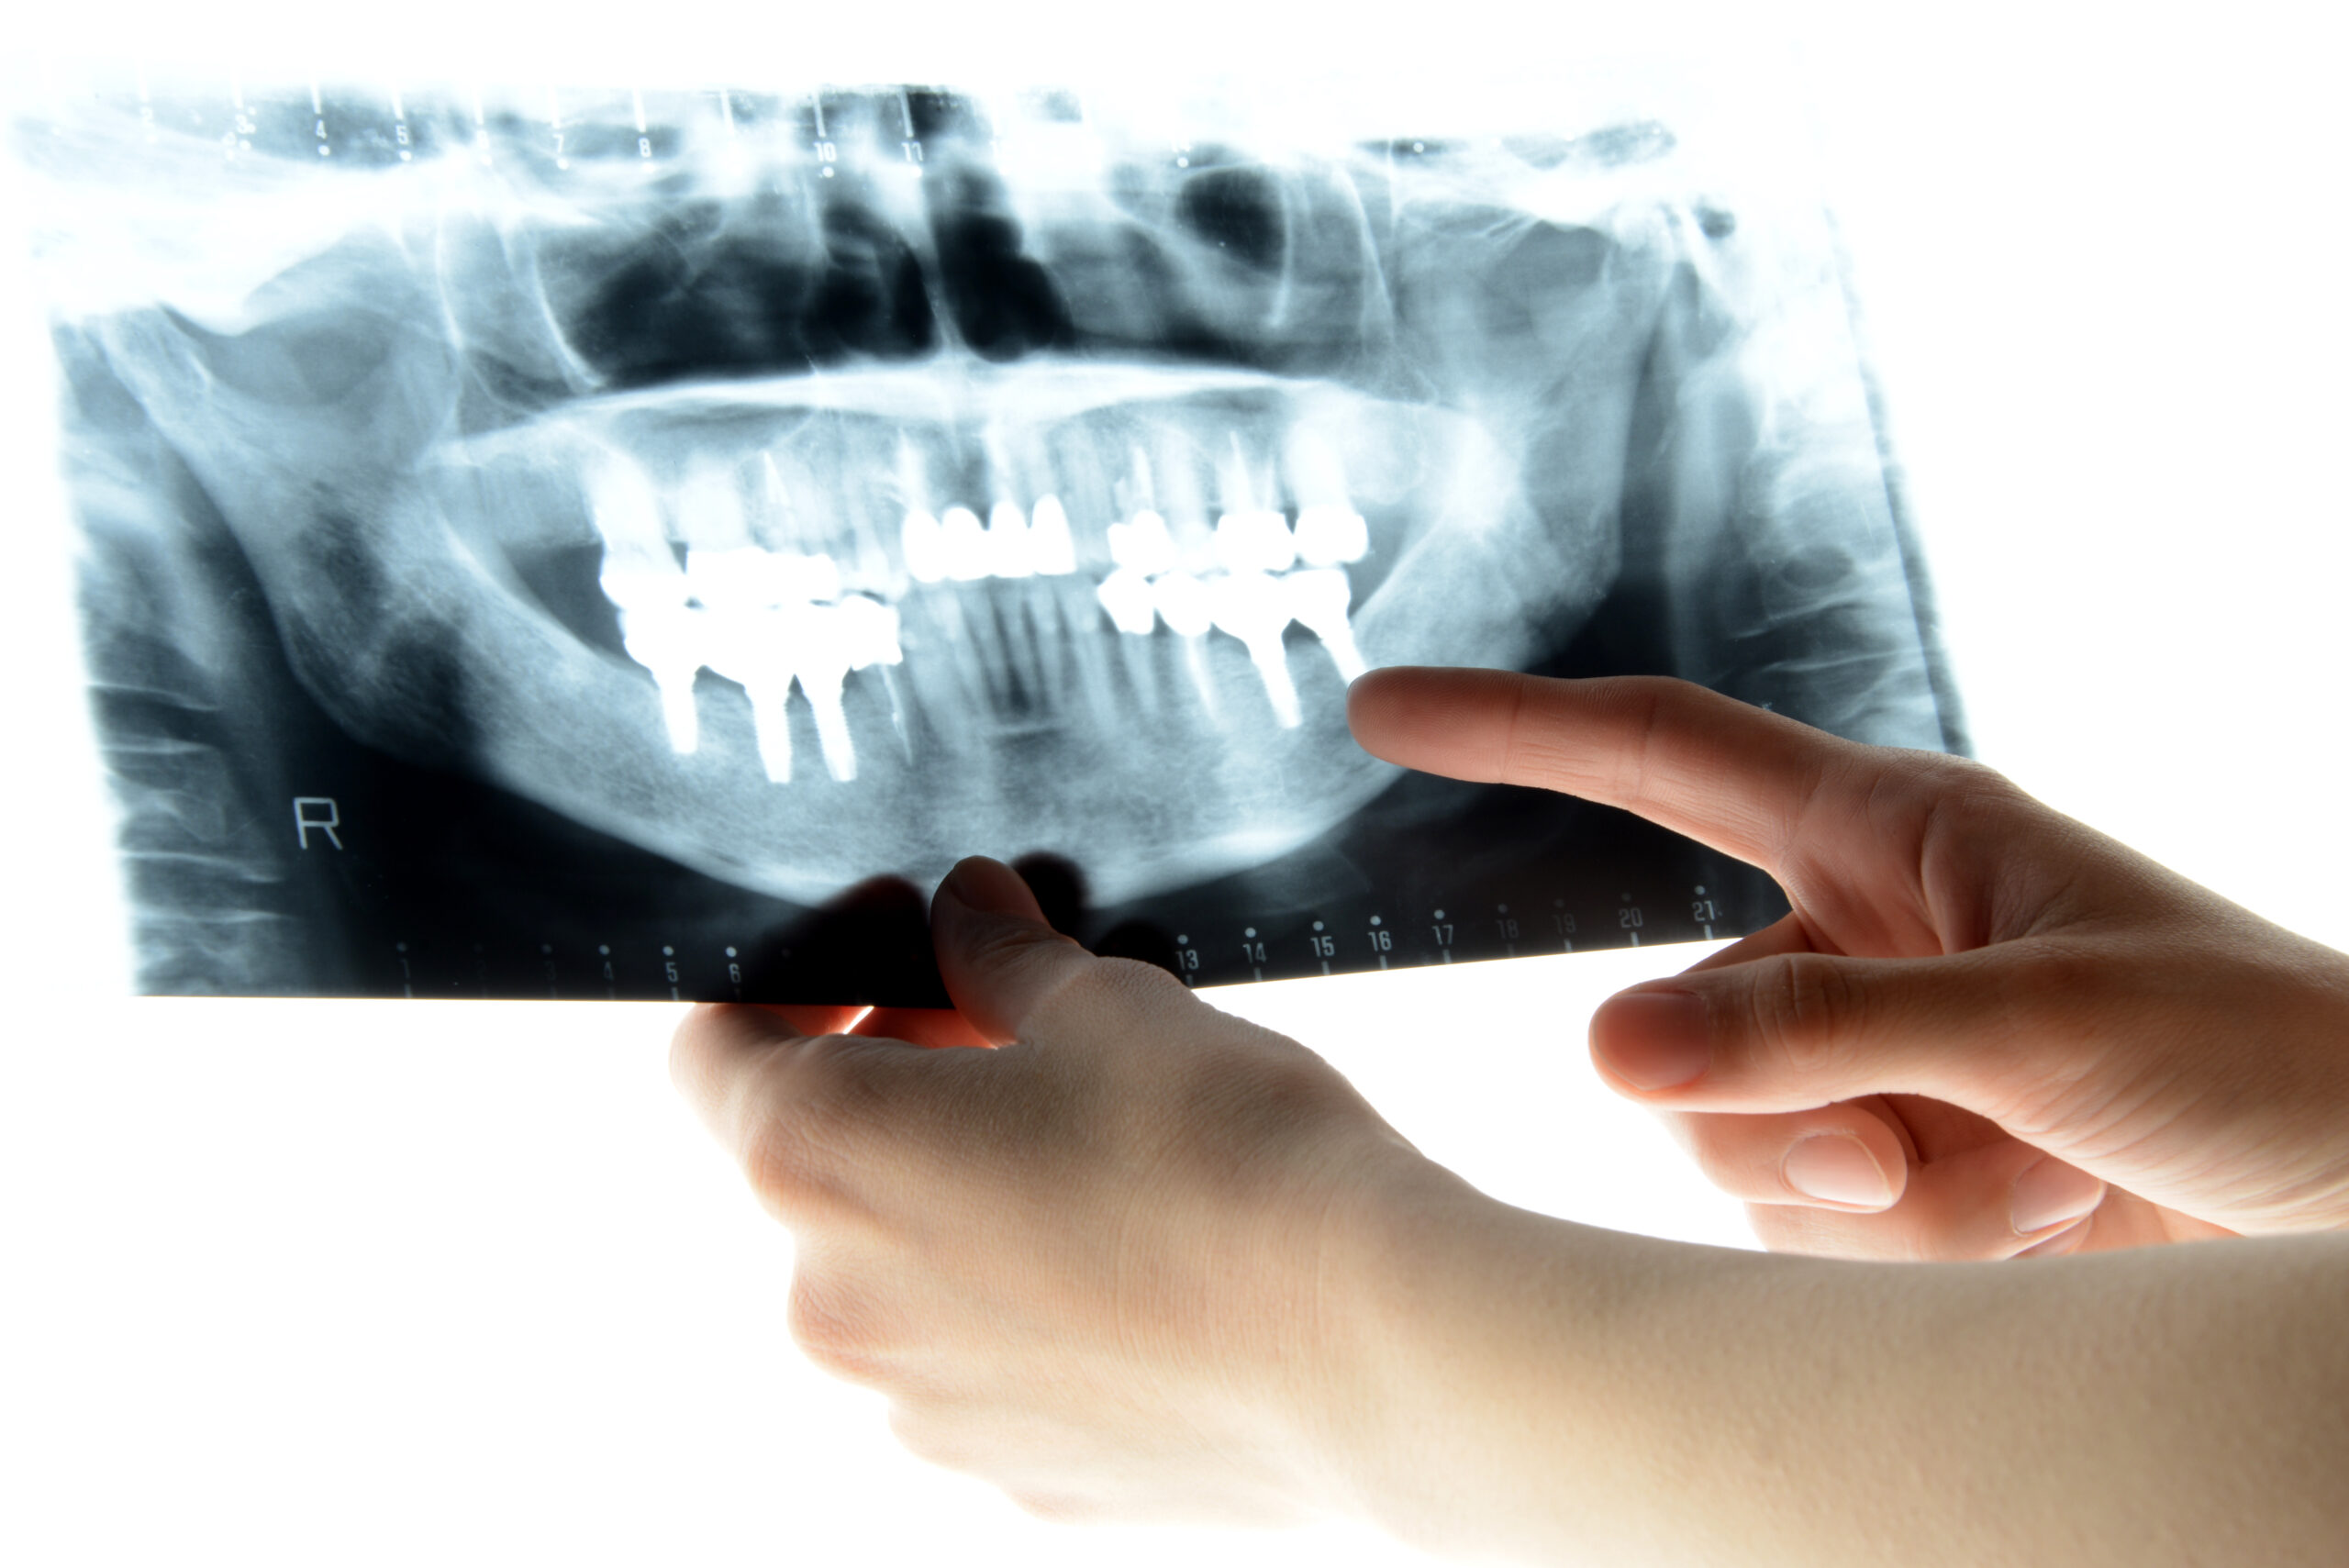

補足:インプラント情報が確認できない場合

通っていた歯科医院が閉院してしまった、カルテの保管期間が過ぎて処分されてしまった、など様々な事情でインプラントの情報が確認できない場合があります。

現在通っている歯科医院で「推定」してもらう

インプラントメーカーを特定するのは困難ですが、レントゲン写真や口腔内の状態を見ることで、歯科医師はある程度の構造を判断できます。

例えば、

- インプラントの形状

- 見た目の構造

- 入れ歯の構造

などから、「これは磁性アタッチメントの入れ歯です」などと推定することが可能です。限度はありますが、かかりつけ医院に相談するのも1つの手段です。